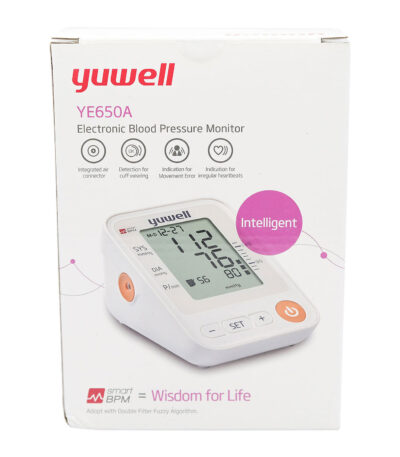

yuwell blood pressure machine